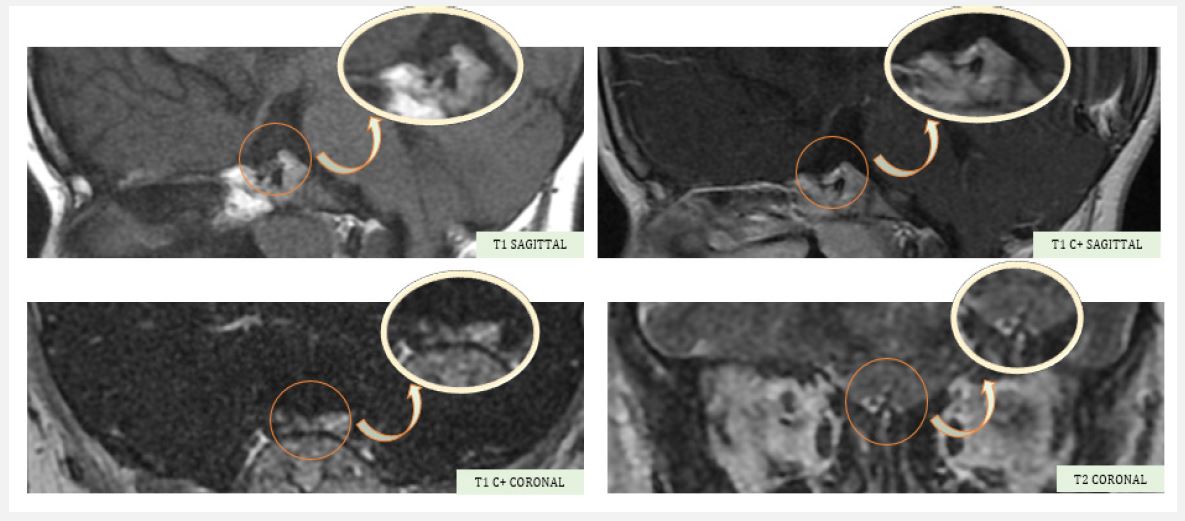

A hypothalamo-pituitary MRI was ordered, revealing an anterior pituitary gland in place, a decrease in height measured at 2 mm, a homogeneous signal before and after contrast, and a lack of clear visualization of the pituitary stalk and the posterior pituitary gland, associated with very severe hypoplasia of the olfactory bulbs, suggestive of Kallmann syndrome.

Figure 1: Hypothalamic-pituitary MRI showing a small anterior pituitary for age, with no individualization of the posterior pituitary or pituitary stalk, and severe hypoplasia of the olfactory bulbs.